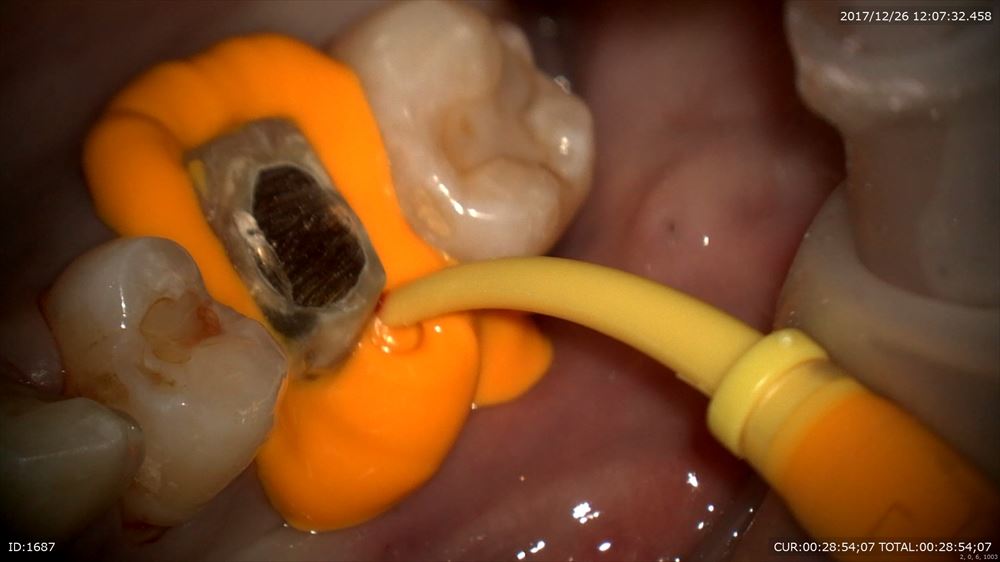

まずは精密な型とり。ブリッジの型を採りました。この患者さまはご家族でいらして頂いており本当にありがとうございます。型取りの時には、いかに歯茎の内部まで型取り材を無痛で流しこむか。が重要になります。

まず型取りの準備